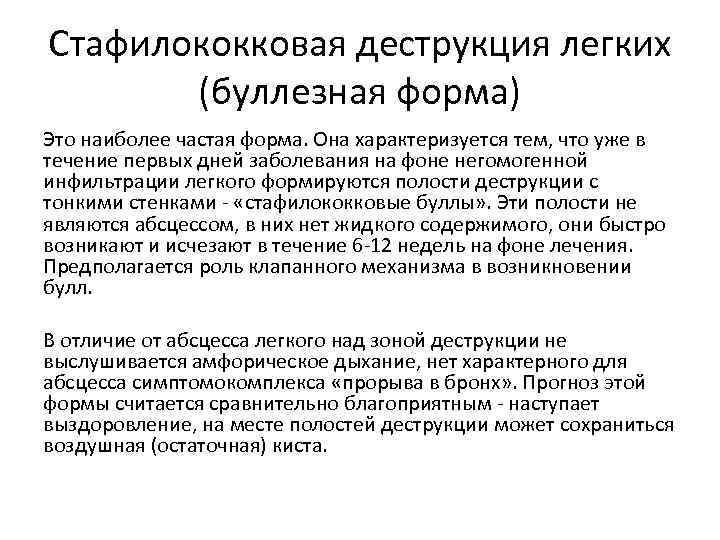

Бактериальная деструкция легких у детей презентация - 88 фото